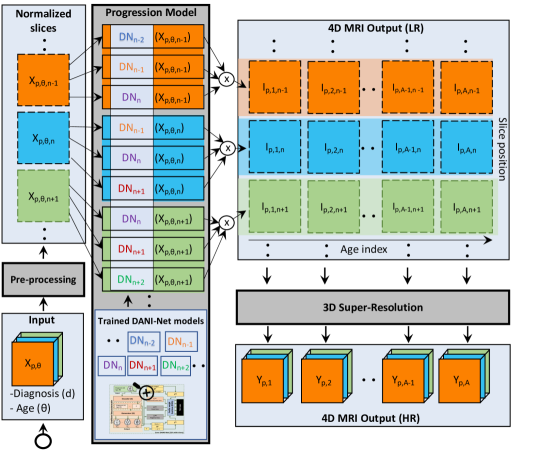

Our framework consists of three main blocks depicted in Fig. 2: i) pre-processing; ii) progression model; and iii) 3D super-resolution. Pre-processing removes irrelevant variations in the data. Progression modelling is performed slice-wise (2D plus time) with 3D training consistency, as a set of DANI-Net models , where represent different slice positions. Finally, our super-resolution block is a function that maps the resulting set of lower-resolution image slices for subject and time point obtained from each , to the high-resolution MRI . Below, we describe each block in detail.

The workflow of the proposed progression model block is described schematically in Fig. 2.

3.3 3D Super-resolution

To recover lost anatomical detail due to the Gaussian smoothing (described in the preceding section), we include a 3D super-resolution block at the end of our pipeline (see Fig. 2). This is based on a modified 3D densely-connected super-resolution network [45] that uses pairs of low-resolution (LR) and high-resolution (HR) MRI for training a deep super-resolution neural network.

We train this super-resolution block separately from the rest of our framework. To do so, we use as HR images the available in the training set, and as LR counterparts, the output obtained from the same input , at the same age computed from our framework when the super-resolution block is disabled.

Once these pairs of LR/HR are created, we use them to train the super-resolution network. We then proceed by attaching this trained SR-network onto the backbone of our trained system. This allows us to super-resolve the stacked output (generated by each ) and to produce the required high-resolution MRI .